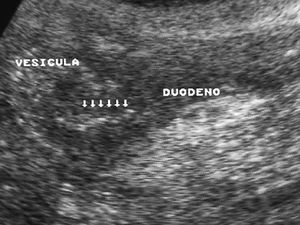

El duodeno puede lesionarse por procedimientos endoscópicos y/o quirúrgicos, al igual que por cuerpos extraños ingeridos (fig. 4). La apariencia radiológica de las lesiones será similar a las producidas por traumatismos externos, reflejando un engrosamiento de pared, alteración de la grasa periduodenal y líquido y/o aire periduodenal o en retroperitoneo en caso de rotura11.

Fig. 4--Perforación duodenal por espina de pescado. (A) Ecografía donde se observa una estructura lineal hiperecogénica (flechas) que sale del duodeno (D). (B) En el estudio de tomografía computarizada se identifica como material hiperdenso (flecha) que corresponde a la espina de pescado, con reacción de la grasa adyacente (puntas de flecha) y líquido en espacio pararrenal anterior derecho.